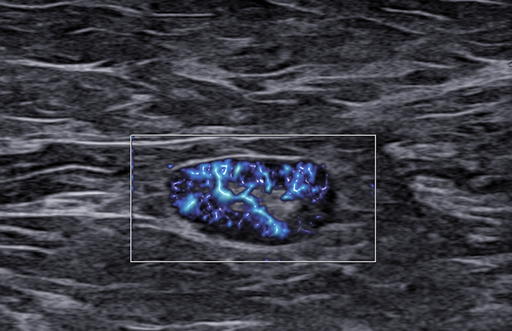

Rak piersi a obraz węzłów chłonnych. LN-RADS

Rak piersi a obraz węzłów chłonnych. LN-RADS - część 2